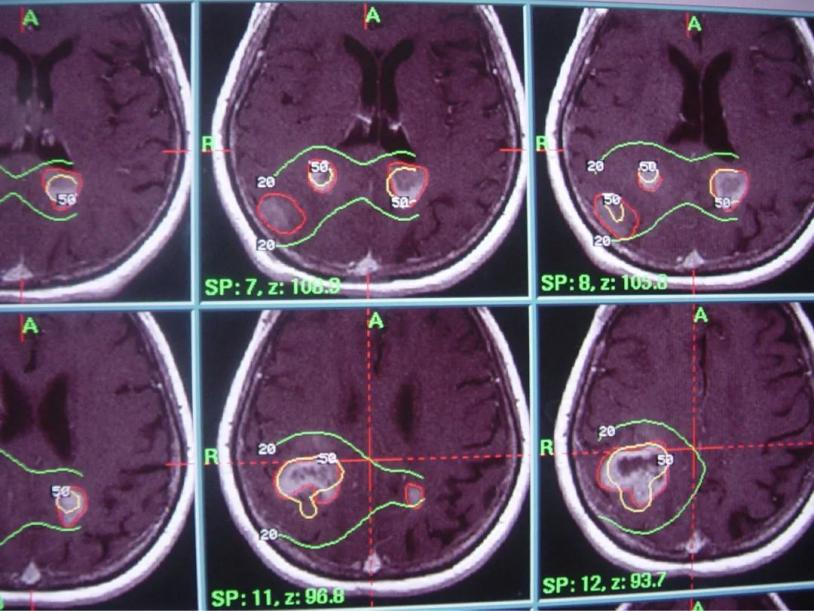

1) 固定立体定向头架(30分钟左右,直到治疗结束才取下)

2) 病灶影像定位(MRI或者CT下)

3) 计划设计与审核

4) 按照计划摆位治疗

5) 治疗结束(取下固定架止血包扎)

伽马刀又称立体定向伽马射线放射治疗,是融立体定向技术和放射技术于一体,以治疗颅内疾病为主的立体定向放射外科治疗设备。其原理是将钴-60发出的伽马射线几何聚焦,集中射于病灶,一次性致死性的摧毁靶点内的组织,射线经过人体正常组织几乎无伤害,并且剂量锐减,相比其他治疗照射范围与正常组织间界限非常明显,边缘如刀割一样,人们形象称之为“伽玛刀”。

2. 采用旋转聚焦的手段,可以做到靶区剂量高,而周围正常组织受量较低,保护了正常的脑组织;